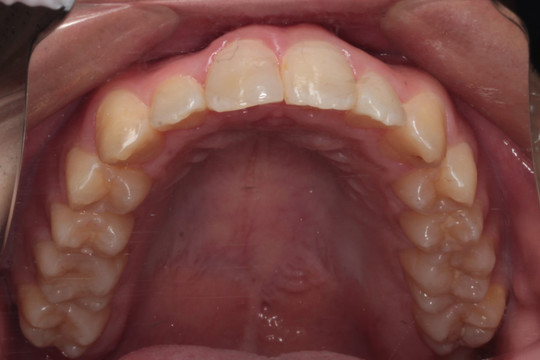

上顎 治療前

上顎 治療後

調布市の20代男性

主訴:前歯のデコボコを直したい

使用装置:インビザライン

治療期間:約2年

治療費用:93.5万円(税込)

治療結果:叢生が改善されました

今回の症例は写真のように上の中心から2番目の歯が左右とも奥に入り込んでいてかなりスペースのない状態でした